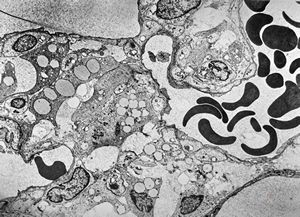

F,50y. | progressive multifocal leukoencephalopathy- viral particles in a glial cell

F,50y. | progressive multifocal leukoencephalopathy- viral particles in a glial cell

F,50y. | progressive multifocal leukoencephalopathy- viral particles in a glial cell